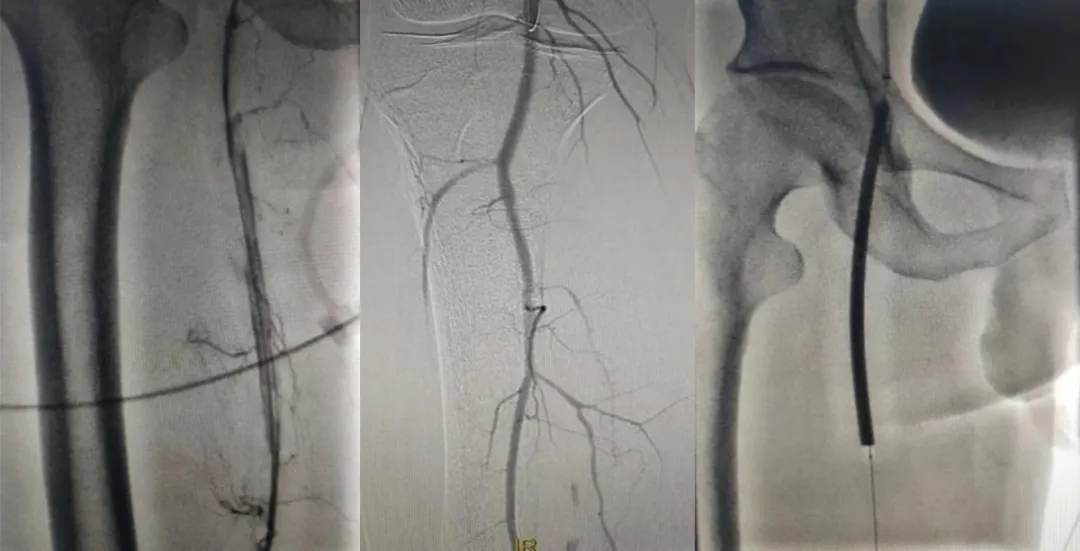

然后

他們巧妙運(yùn)用

先進(jìn)的機(jī)械導(dǎo)管和球囊

如精巧的工匠般

小心翼翼地

疏通著“生命之路”

術(shù)中造影